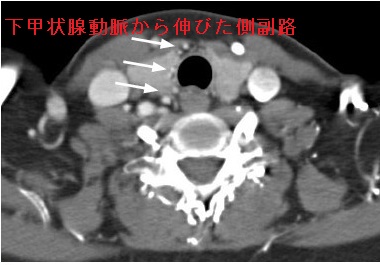

- 甲状腺超音波エコー検査の際に、①下甲状腺動脈から伸びた側副路、②壁肥厚と管腔内血流欠損を伴う狭小化した総頸動脈を認め、偶然、大動脈炎症候群(高安動脈炎)が見つかった。[Ultrasonography. 2014 Jul;33(3):222-5.]